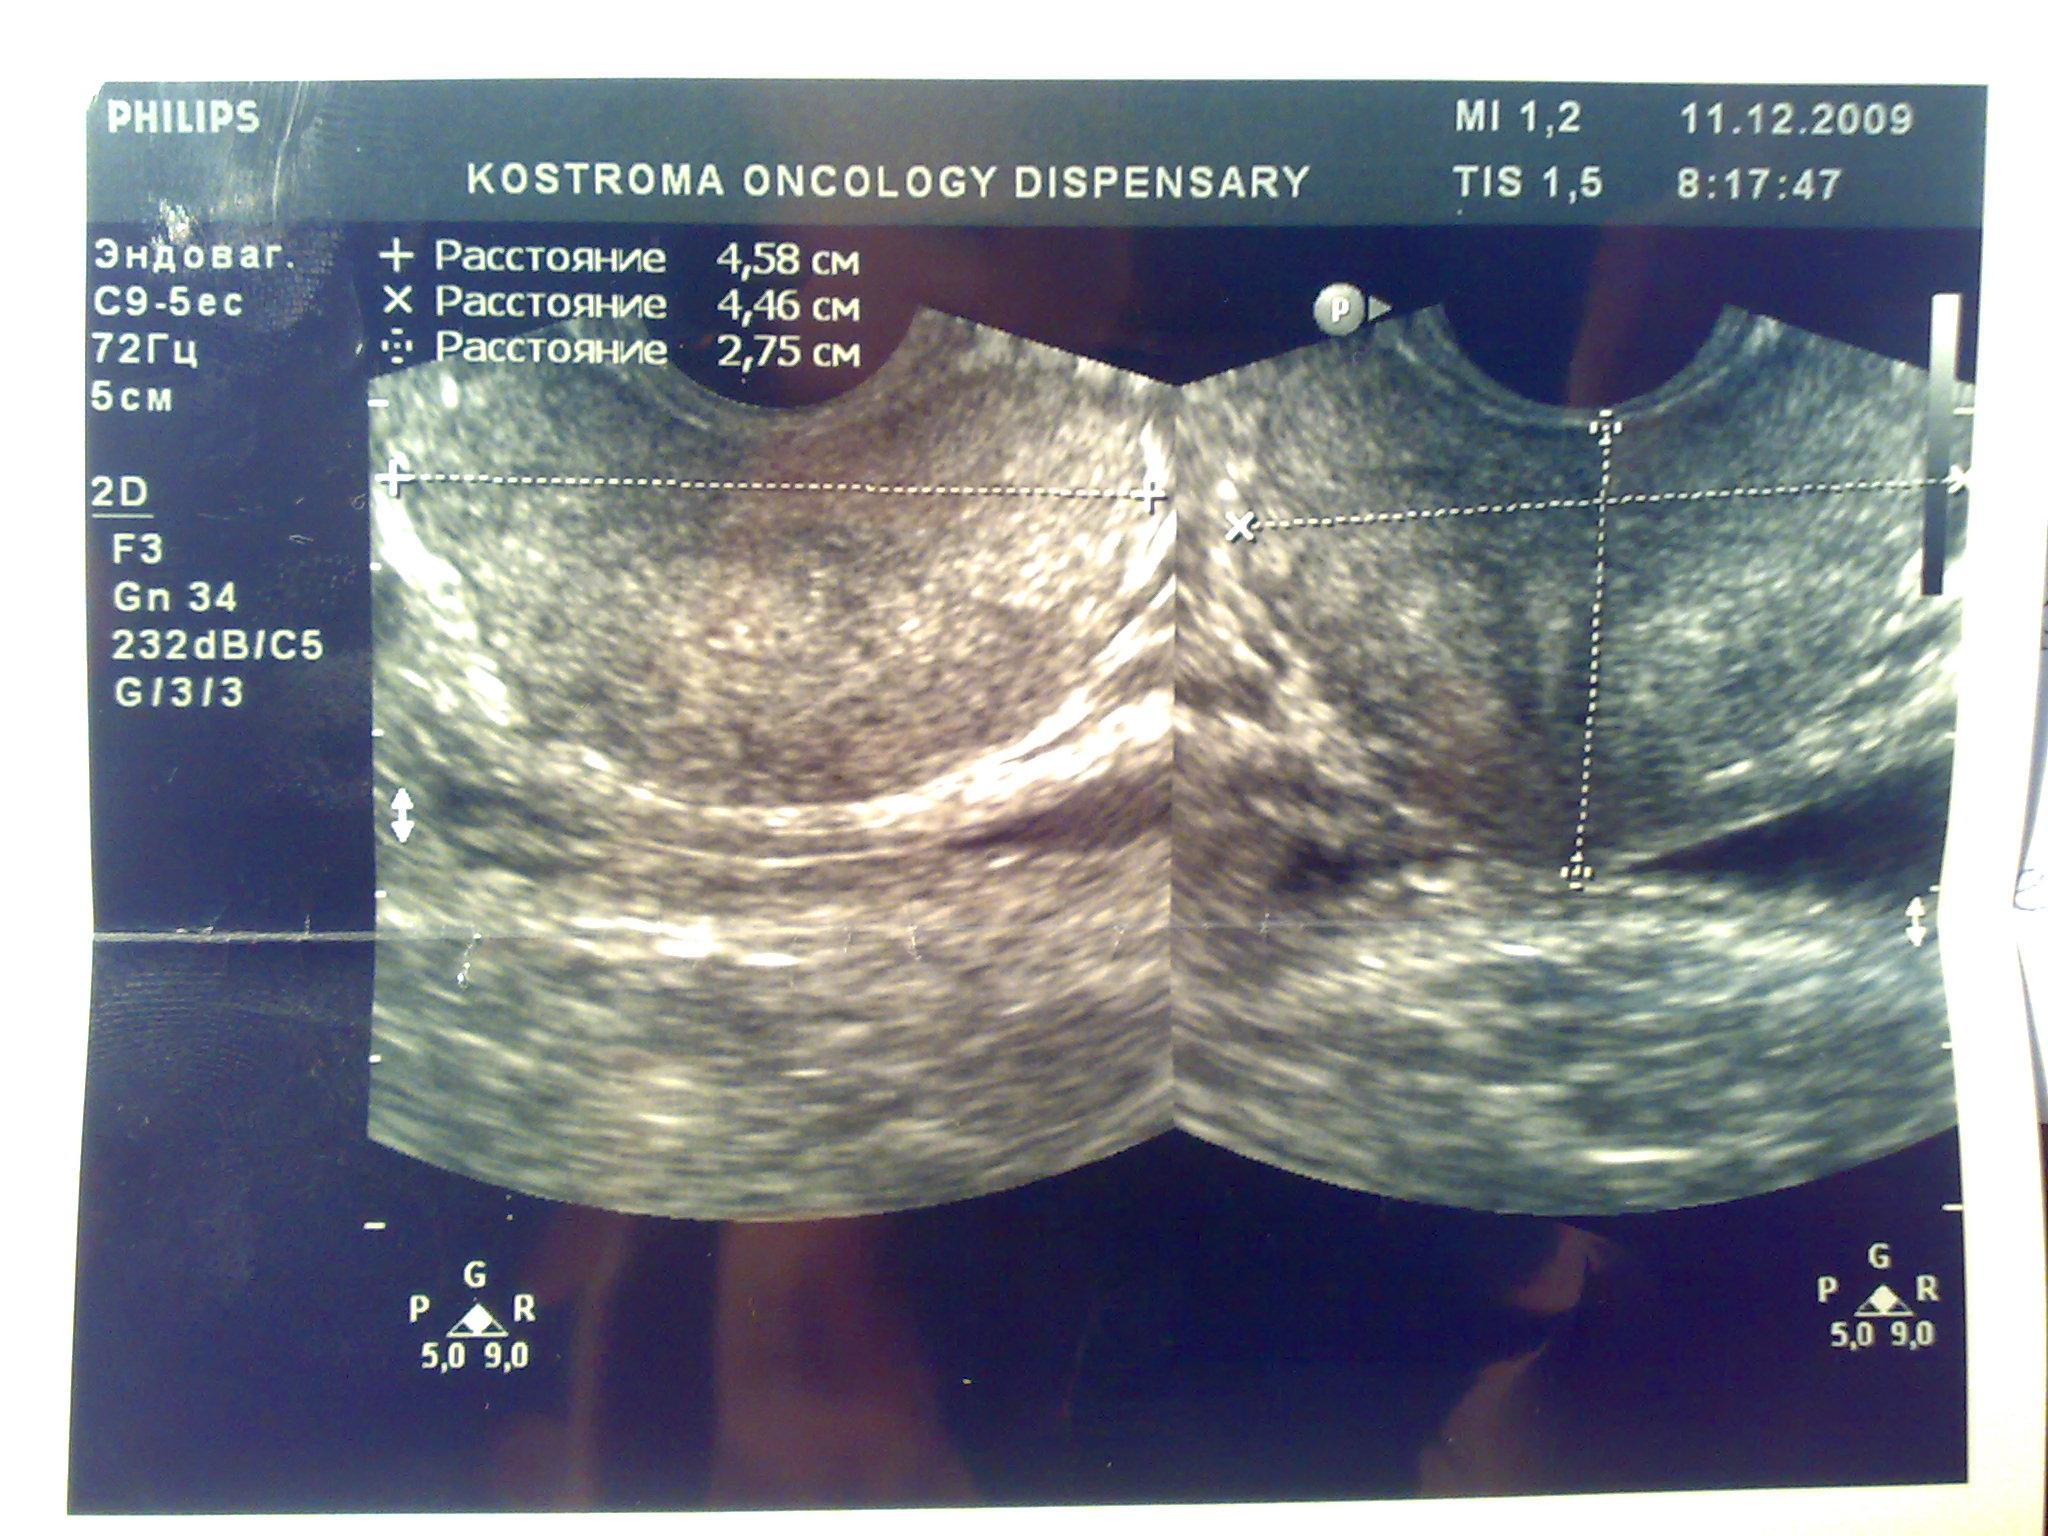

Посмотрите пожалуйста снимки узи, какие выводы можно сделать кроме увелечинных размеров? Может ли это влиять на эректильную функцию или изменение гормонального статуса? Болевых ощущений нет, есть небольшой дискомфорт, мочеиспускание в норме, но струя послабже чем была.Очень переживаю, ночами не сплю из-за нервов, без седативных уже и не уснуть.Заранее благодарен.

Ваши симтомы не связаны с предстательной железой. Вам нужен хороший психолог или психоаналитик. Уролог не нужен.